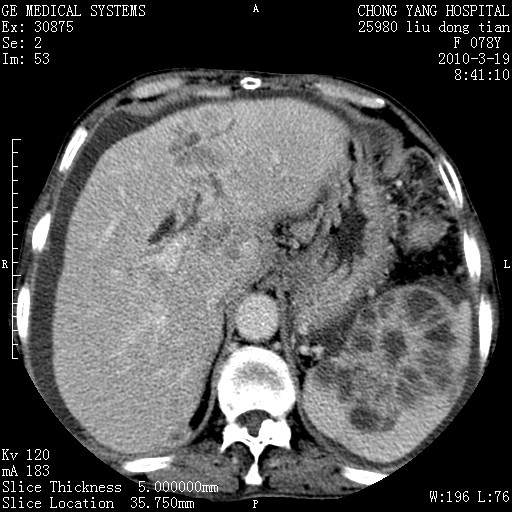

标题: CT25199:F 78Y 腹胀半年 消瘦乏力 [打印本页]

胆囊壁增厚并明显强化,胆囊癌伴多发转移瘤可能性大,淋巴瘤不除外,右肾囊肿,胸腹水.

考虑nhl,肝、脾、腹膜腔及腹膜后多发淋巴结受侵,腹水,右肾囊肿,慢性胆囊炎,右侧少量胸腔积液。

胆囊有软组织影有强化,支持胆囊癌,肝脾、腹膜后淋巴结转移。

nhl的淋巴结多围绕主动脉,而且主动脉会移位,所以不考虑nhl。

分开来讲:肝左叶、尾叶病灶有不均强化像肝癌;

脾脏病灶无强化,像多发囊肿或淋巴管瘤,不除外淋巴瘤(低强化);

胆囊增生性病变:胆囊癌,腺肌增生症,慢性胆囊炎;

肝门、胰腺头、腹膜后多个团块: 淋巴瘤,转移;

腔静脉肝内段细小有无布加可能?

一元论最好了 淋巴瘤所致改变; 胆囊癌转移不像,胆囊周围肝组织清晰,肝癌淋巴结转移?三元论都不止。

脾脏病灶像车轮 莲花,第一感觉还像包虫呢。真想全切出来一个个做病检。

最后报的胰头癌多发转移,脾脏单独考虑囊肿或淋巴管瘤。